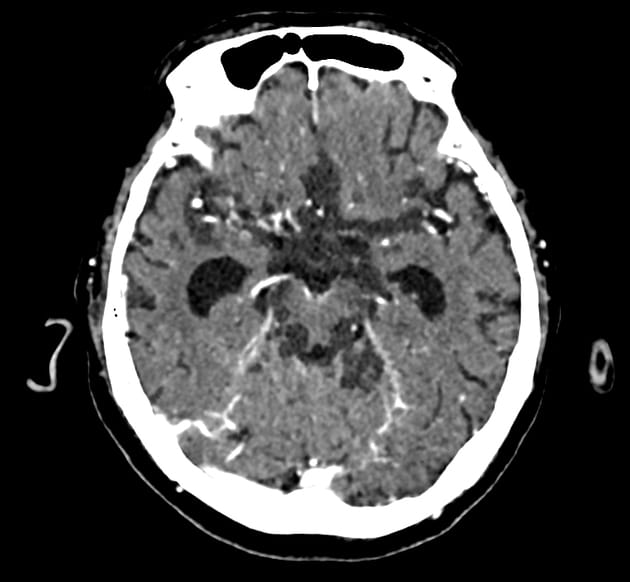

Kryptokokoza OUN

Najcięższą postacią choroby jest kryptokokowe zapalenie opon mózgowych oraz ropnie mózgu, które powodują objawy ogniskowe. Przebieg ma zwykle charakter podostry, z narastaniem objawów przez dni lub tygodnie. Często zmianom towarzyszy obrzęk mózgu. Dominują:

- przewlekły ból głowy,

- prawidłowa lub umiarkowanie podwyższona temperatura ciała,

- nudności i wymioty,

- zaburzenia świadomości,

- zaburzenia widzenia wynikające ze wzrostu ciśnienia śródczaszkowego [1,3].

Sztywność karku i inne klasyczne objawy oponowe mogą być nieobecne, szczególnie u pacjentów z HIV, co istotnie utrudnia rozpoznanie w warunkach ambulatoryjnych.

Identyfikacja czynnika etiologicznego polega na wykonaniu preparatu bezpośredniego, hodowli na odpowiednich pożywkach, badaniach serologicznych, histologicznych oraz molekularnych [1–3]. Warto wykonać badania obrazowe głowy i klatki piersiowej w celu oceny rozległości choroby i obecności guzków.

U każdego pacjenta z podejrzeniem kryptokokowego ZOMR należy wykonać nakłucie lędźwiowe z oceną ciśnienia otwarcia oraz badaniem PMR (mikroskopia, posiew, CrAg). Podwyższone ciśnienie śródczaszkowe stanowi istotny czynnik rokowniczy i wymaga aktywnego leczenia [1].